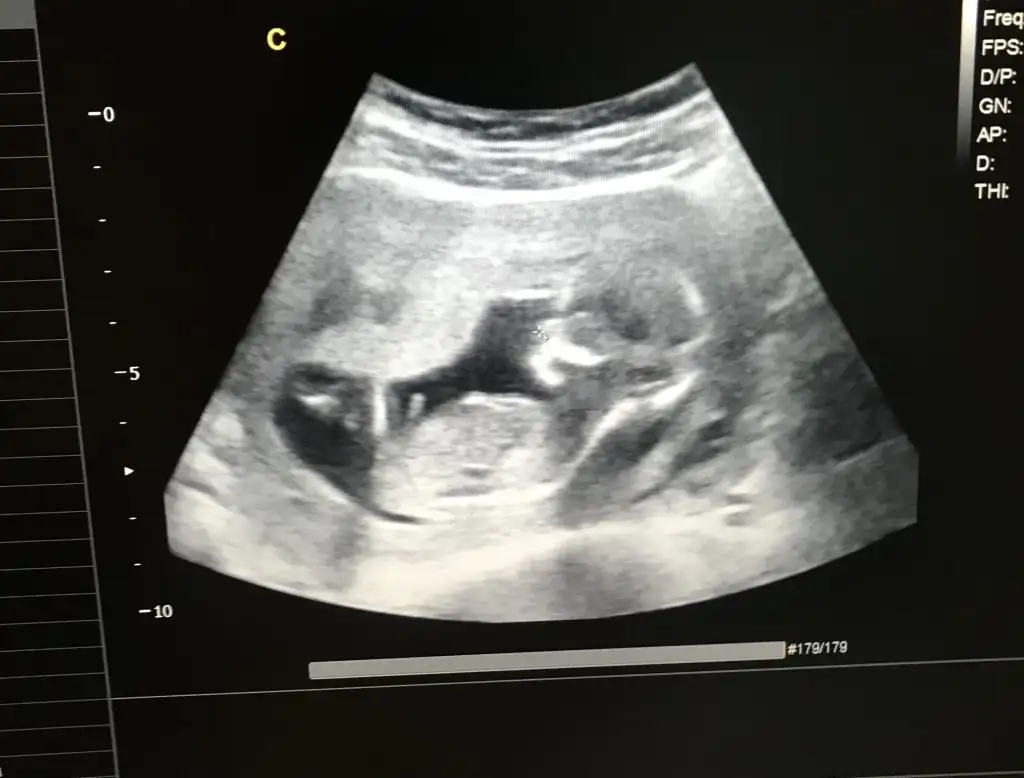

Kızlar bana da bakar mısınız ?

merhabalar bana da yorum yapabilir misiniz doktor tahmin söyledi ama net 16 da söyleyecek şimdiden teşekkürler 🙏🏻